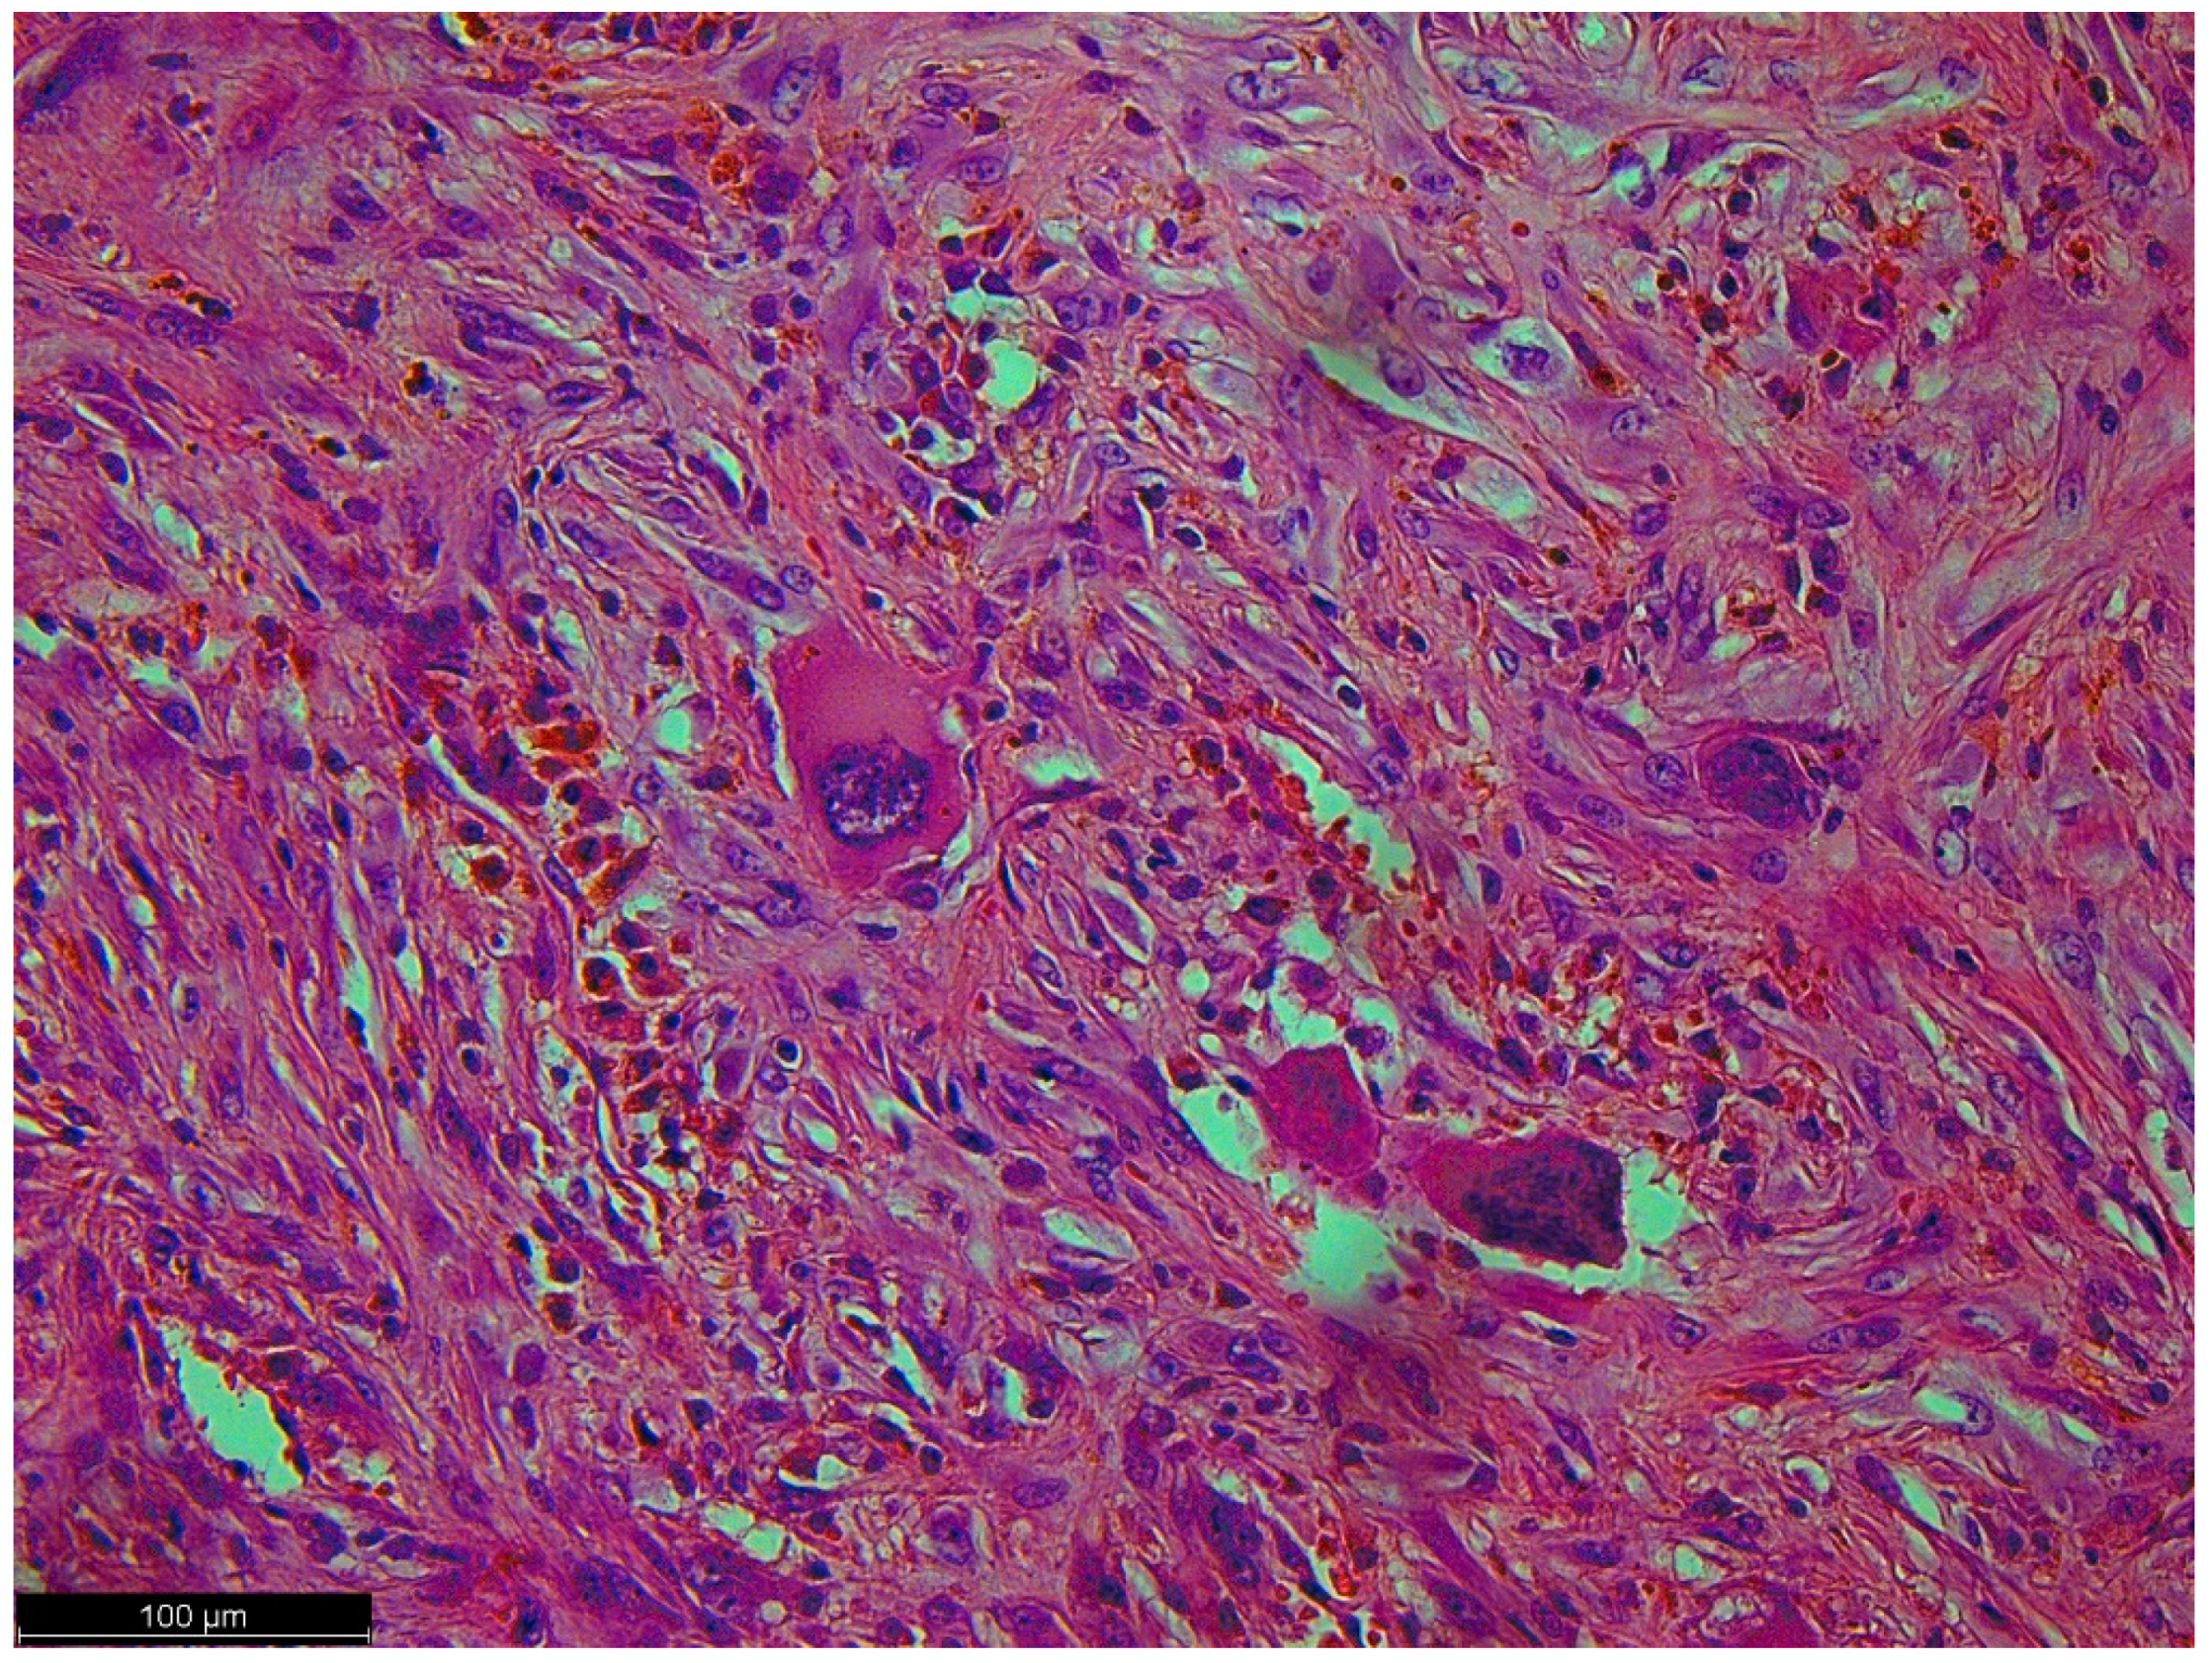

Figure 5.

This picture looked like osteosarcoma, but it was not. It was a dedifferentiated liposarcoma with a heterologous component. In this case, the tumor produced osteoids with calcified trabeculae. The photo shows an osteoblastic rimming.